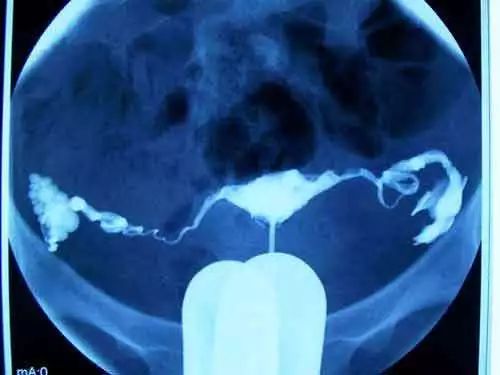

輸卵管造影是用來檢查女性輸卵管通暢與否的一種檢測方法。目前臨床上常用的是X線輸卵管造影和超聲輸卵管造影。

X線輸卵管造影簡單點說就是通過導管向宮腔及輸卵管注入造影劑,經X線透視及攝片,查看造影劑在宮腔、輸卵管內及盆腔內的顯影情況,診斷輸卵管是否通暢、阻塞部位及宮腔形態。常用造影劑是碘,可能造成過敏、感染等,有些還會出現不適反應,甚吸入一些X線,造影后兩三個月再考慮試孕。